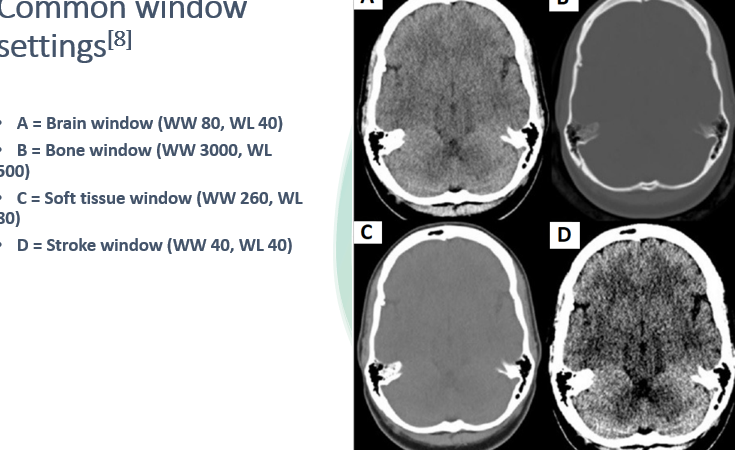

why is windowing important

•Window settings are used to aid detection of pathologies involving the brain substance (e.g. infarcts), the skull vault (e.g. fractures) or soft tissues (e.g. haematomas).

•Window settings are described in terms of window width (WW) and window level (WL) – these values are typically displayed on the computer screen.

•WW = the range of grey-scales displayed

•WL = the centre of the WW

•Altering the window settings helps reduce the range of HU displayed, which in turn helps to maximise the pickup rate of different pathologies.